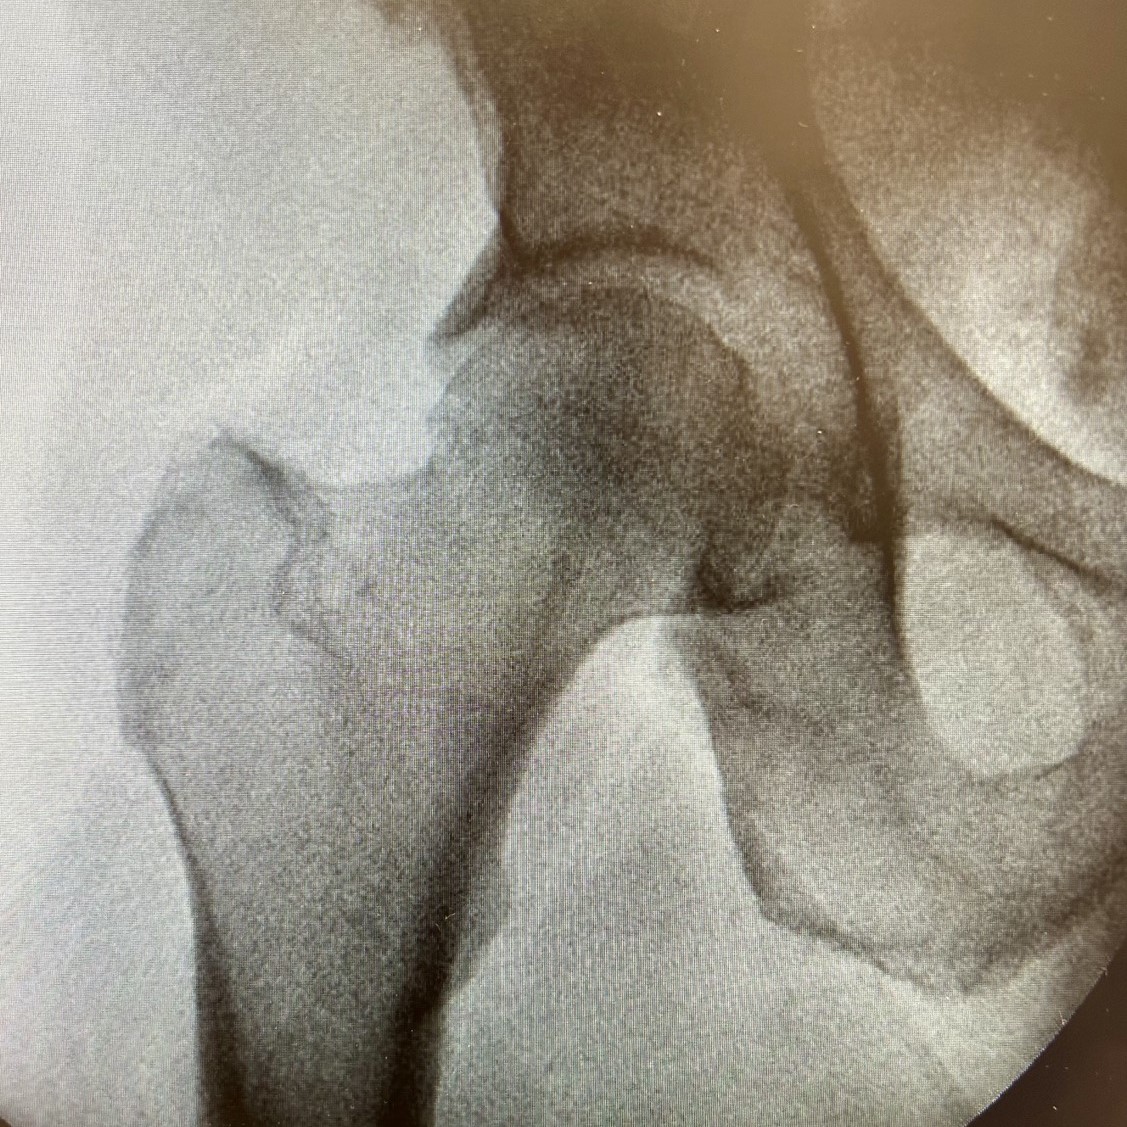

As fraturas do terço proximal do fêmur, que incluem as fraturas de colo do fêmur e as fraturas transtrocantéricas, são lesões graves que afetam a região do quadril e podem ter...